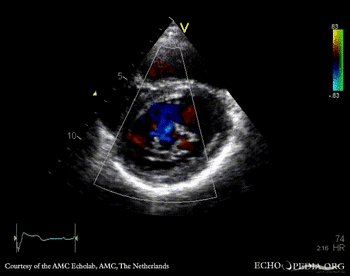

PSAX